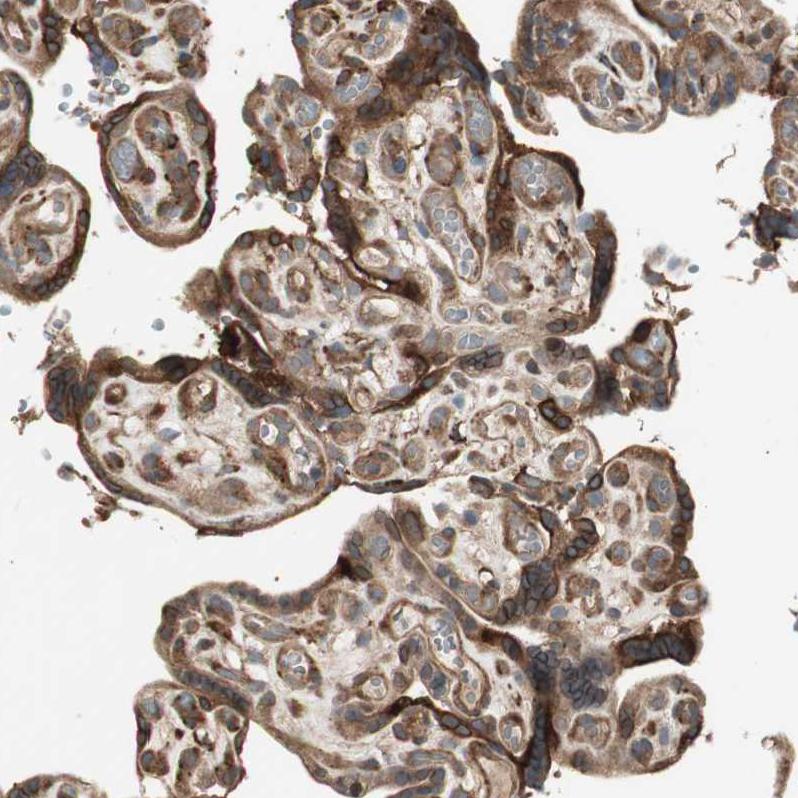

Immunohistochemical staining of human placenta shows strong cytoplasmic and membranous positivity in trophoblastic cells.